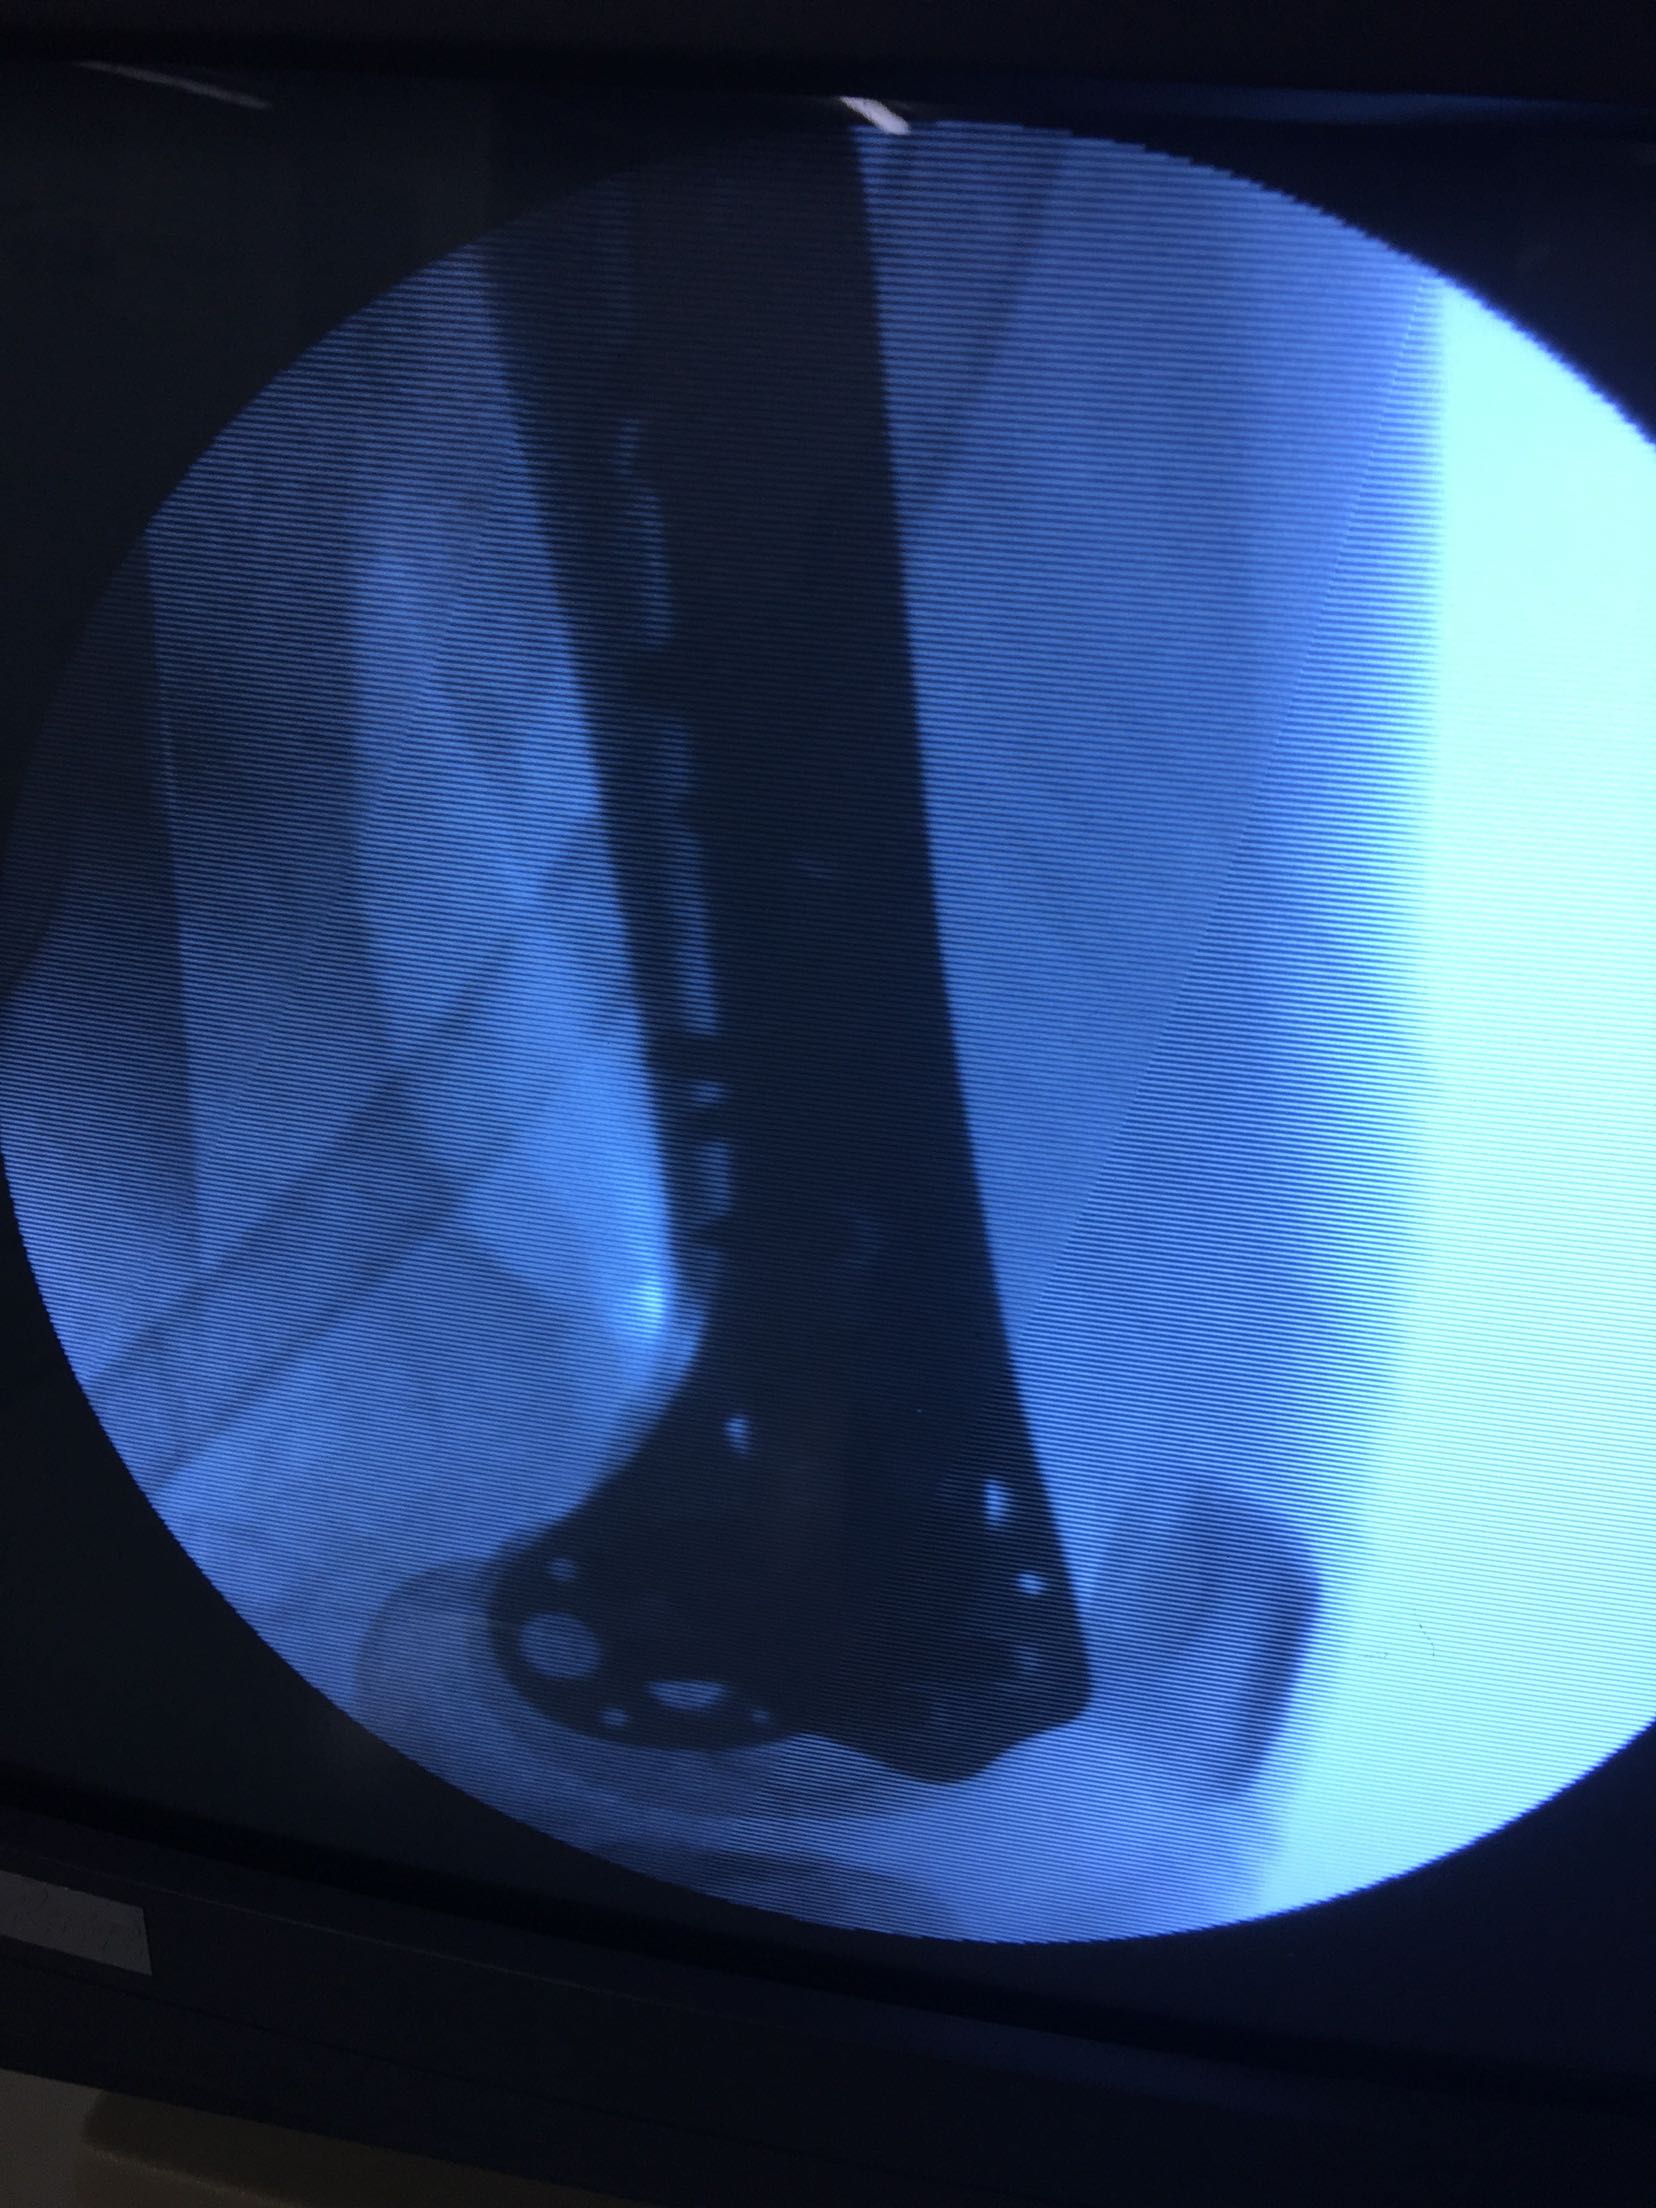

完善检查,急诊在局麻下行胫骨结节骨牵引术。术后一周,病情平稳,在腰麻下行切复内固定术,考虑骨折粉碎,骨质疏松,拟行双钢板固定。术后抗炎,对症治疗,嘱咐一周后早期膝关节微动锻炼。